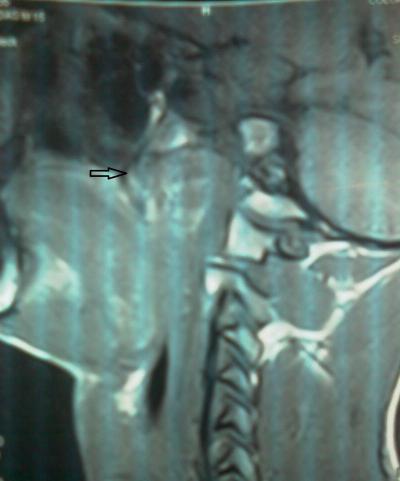

Figure 1: A sagittal view of preoperative CT scan showing a tumour occupying the nasopharyngeal space (arrow)